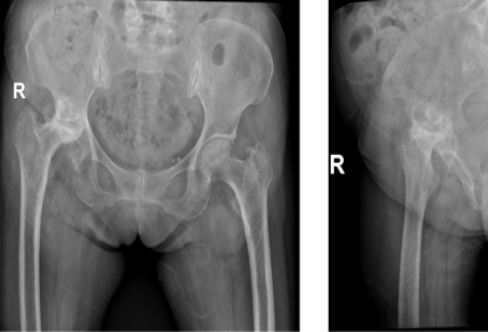

Case 2: 87-year-old female with left neck of femur fracture

Denosumab ➝ Romosozumab